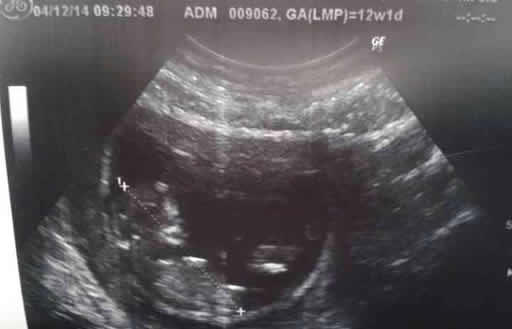

网传nt值看男女85%的准确率!nt单子上真有男女标志?nt单子上暗示男女的标志包括xy字母、mf字母、nt数值,但这种说法是没有经过科学检验的,并不准确,因为nt检查主要是通过检查胎儿颈部透明度厚度,来判断胎儿是否患有唐氏综合征等先天性疾病,不是看男孩女孩的。

nt单子上暗示男女的标志